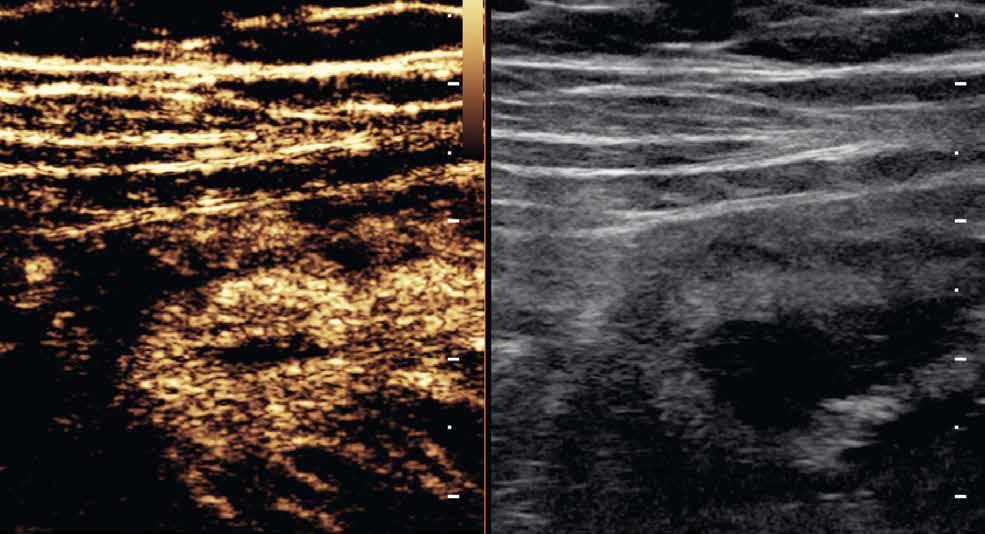

Obr. 1–3: CEUS. Pacient s Crohnovou nemocí ve fázi aktivního zánětu. Po podání kontrastní látky je patrné postupné sycení střevní stěny (1, 2, levá část obrázku), která je výrazně zesílená s akcentovanou hypoechogenní sliznicí (1, 2, pravá část obrázku). Křivka sycení pak svědčí rovněž pro akutní fázi zánětu (3).